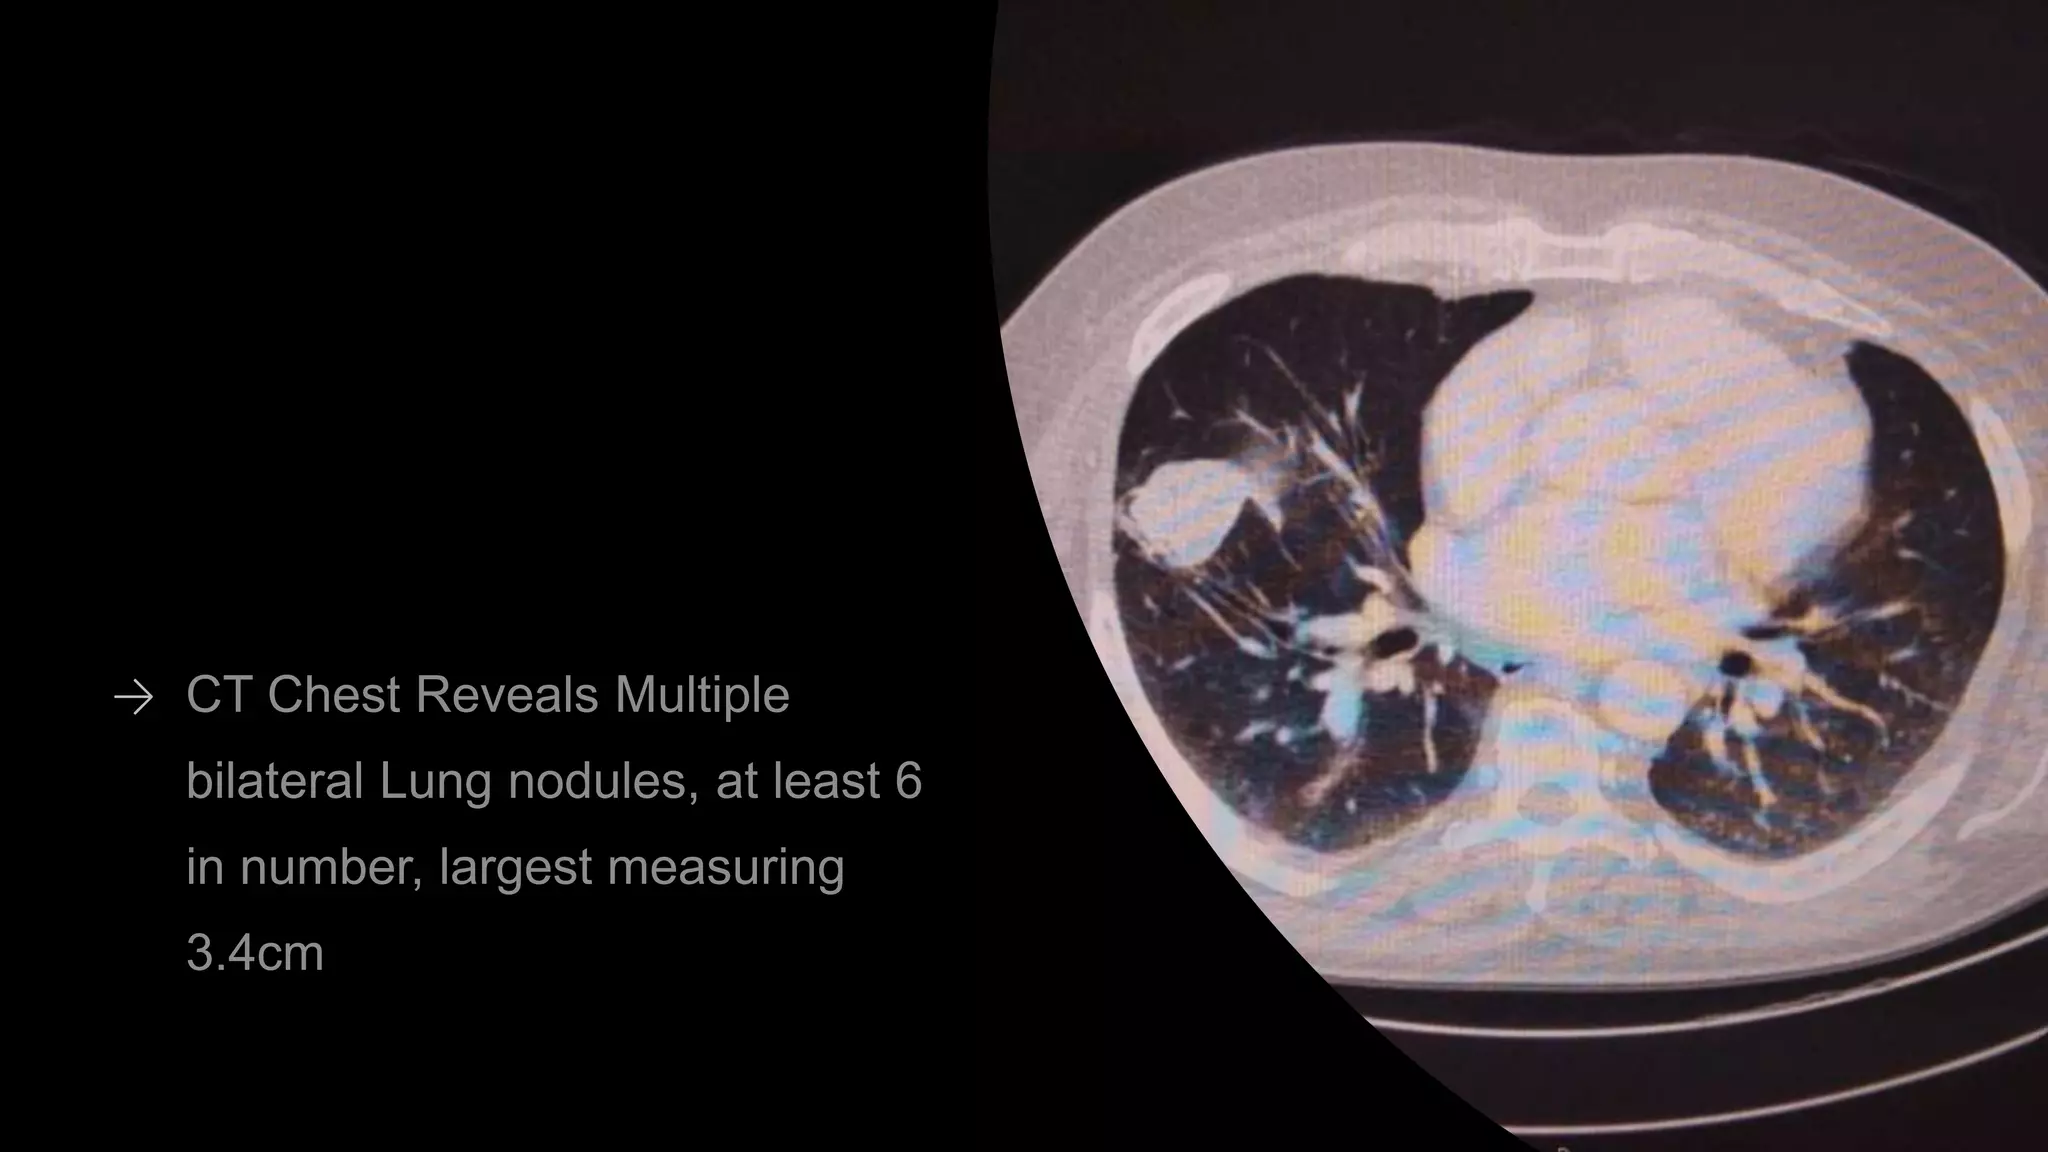

CASE PRESENTATION

METASTATIC RCC